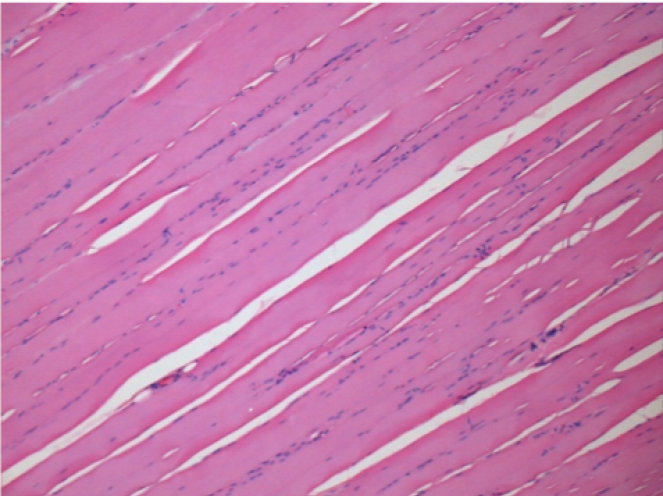

L:Pretibial-No treatment

-hematoxilin-eosin